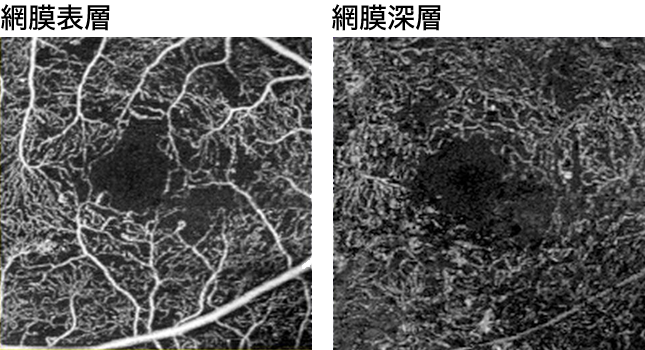

網膜血管の異常を正確に把握するために、造影剤を静脈注射した後、眼底カメラで撮影する血管造影検査です。治療方針の決定に役立ちます。

光干渉断層画像から、造影剤を使わず非侵襲的に血管構造を画像化することができるようになりました。さらに層別に表示することができます。